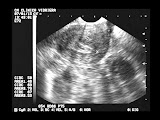

olhei para a tela ao meu lado

e um pontinho de luz brilhante pulsava

forte,

naquela imagem matizada de cor acinzentada.

Essa foi a primeira vez que o vi!